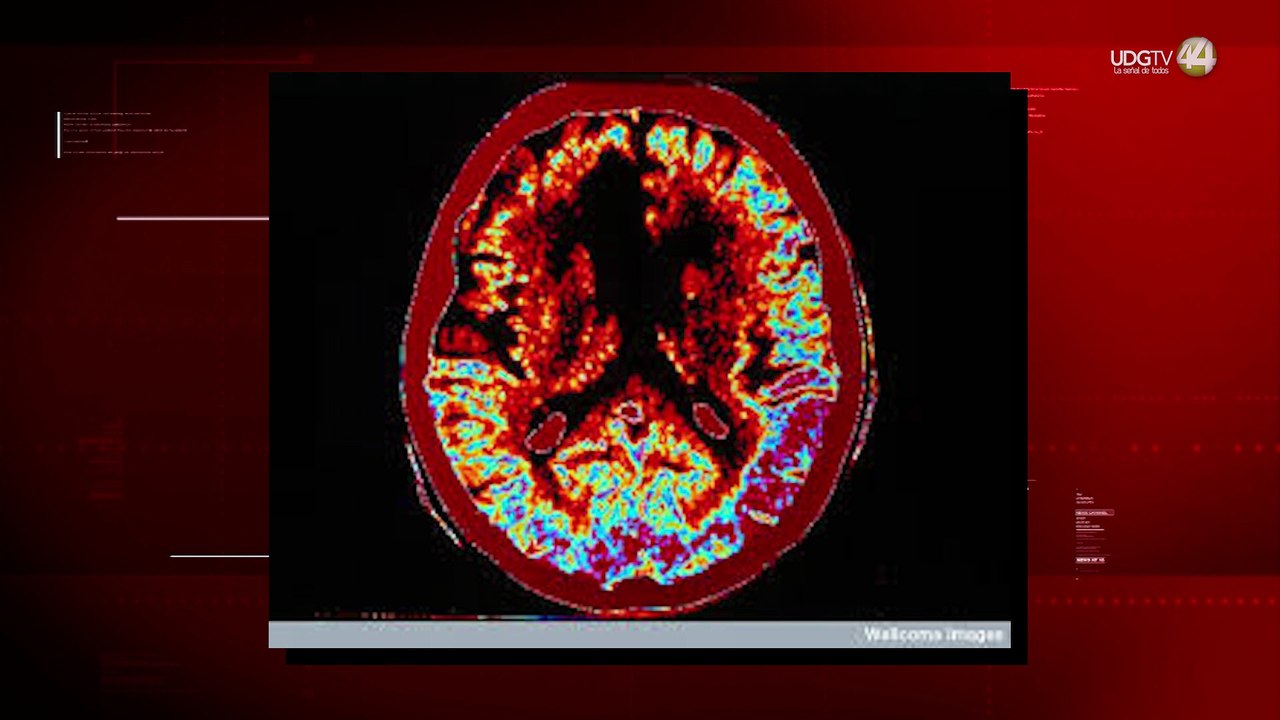

Se rendirá homenaje a la gran Wanda Seux debutará como conferencista y compartirá sus experiencias cuando estuvo al borde de la muerte.<br /><br />No te pierdas todos los días Sale el Sol a las 8 a.m. por Imagen Televisión.<br /><br />Visita también nuestra página www.imagentv.com<br /><br />O en las redes de Sale el Sol<br />Facebook: http://bit.ly/2mJSv1f<br />Twitter: http://bit.ly/2q0z1H0<br /><br />O en nuestras redes de Imagen Televisión<br />Facebook: http://bit.ly/2psCu3R<br />Twitter: http://bit.ly/2pxLq4U<br /><br />¡Déjanos tus comentarios, da like, comparte y suscríbete!